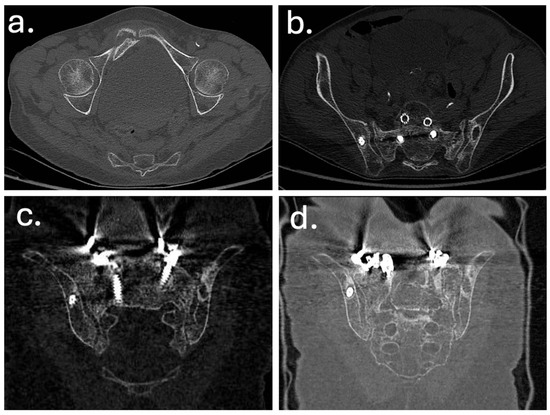

In December 2019, a revision surgery was performed due to partial construct failure and suspected iliac screw loosening as showed in Figure 4 and Figure 5. The left iliac screw and bilateral screws at T4–T5 were removed. New pedicle screws were placed bilaterally at T2–T3, and two additional rods were added, creating a delta-rod four-rod configuration to enhance construct stability and distribute stress.

Figure 4. Computed tomography (CT) images obtained at the time of sacral insufficiency fracture diagnosis. (a) Axial view showing a right ilio-pubic branch fracture. (b) Axial view demonstrating an impacted fracture of the left sacral ala. (c,d) Coronal reconstructions confirming the left sacral ala fracture (c) and illustrating loosening of the iliac screws (d).